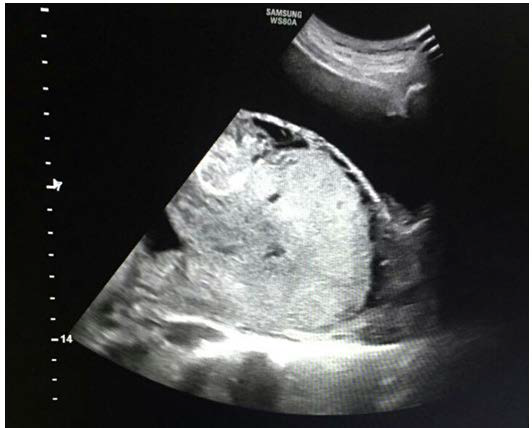

Figure 1: 2D-Ultrasound imaging showing the abnormally attached placenta directly implanted on the uterine serosa of the anterior uterine wall.

figure 1